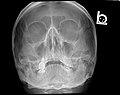

Paranasal Sinuses ant.jpg

Paranasal sinuses seen in a frontal view